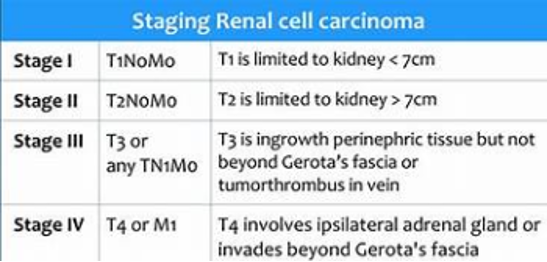

Staging of RCC: